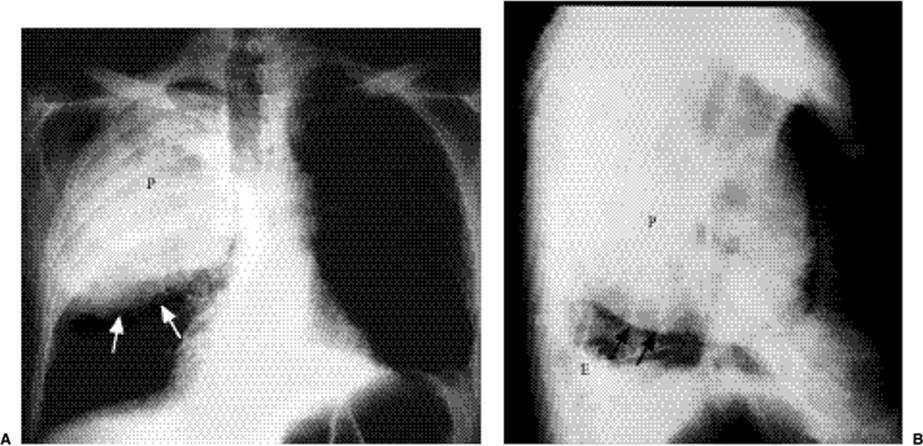

Lobar consolidation is often due to bacteria. Postobstructive pneumonia needs to be considered in patients at risk for lung carcinoma. Expansive consolidation occurs in Klebsiella pneumonia (“Friedlander pneumonia”) (Fig. 5.12) but can also be seen with S. pneumoniae.

Cavitating consolidation (Figs. 5.13 and 5.14) suggests bacteria or fungi. S. aureus, Klebsiella, anaerobes, and Mycobacterium tuberculosiscommonly cause cavitation. Pneumatoceles may result in a similar appearance (Fig. 5.15) and suggest S. aureus or S. pneumoniae.Emphysematous bullae within consolidated lung may mimic cavities.

Figure 5.12 Pneumonia (P) enlarging the right upper lobe, suggesting the correct diagnosis of Klebsiella pneumonia. (A)Posteroanterior and (B) lateral chest radiographs: note bowing of major fissure (arrows). There is an associated pleural effusion (E).